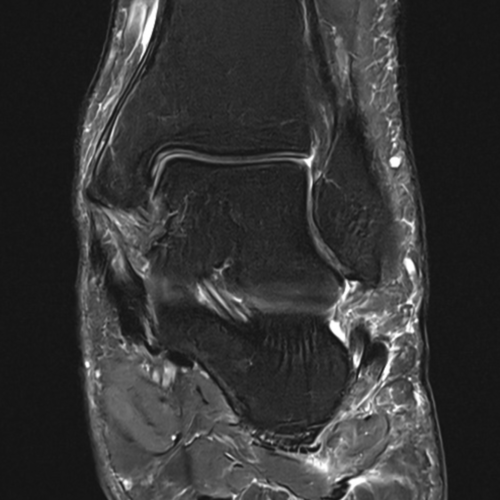

Cet examen est réalisé pour analyser les différentes structures anatomiques de la cheville : ligament externe, ligament interne, talus, calcanéum, articulation talo-crurale, sous-talienne, Chopart, Lisfranc, cartilage, tendon d’Achille, aponévrose.

Il est réalisé en cas de douleurs, traumatisme, entorse.

Cette examen permets de diagnostiquer:

- les entorses

- les tendinites (Achille, fibulaire, tibial antérieur)

- les fractures

- l’arthrose

- les LODA

- les tendite d’Achille

- les ostéochondites